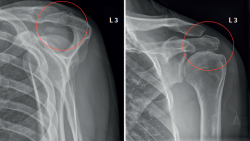

Figure 1. Left shoulder. Preoperative radiographic view showing a "double density" sign (red circle) suggestive of os acromiale.

The basic imaging diagnostic explorations should include anteroposterior, axillary and scapular Y projection radiographs(Figure 1), with the axillary view being the most useful option in this regard(8). Magnetic resonance imaging (MRI) can identify additional disease conditions such as concomitant rotator cuff injury, for example(9). The presence of bone oedema in axial sections in fat-suppressed T2-weighted sequences is an expected sign in the MRI assessment of symptomatic os acromiale (Figure 2).

Figure 10. Control at the end of the procedure. Posteroanterior and axillary view of the left shoulder.